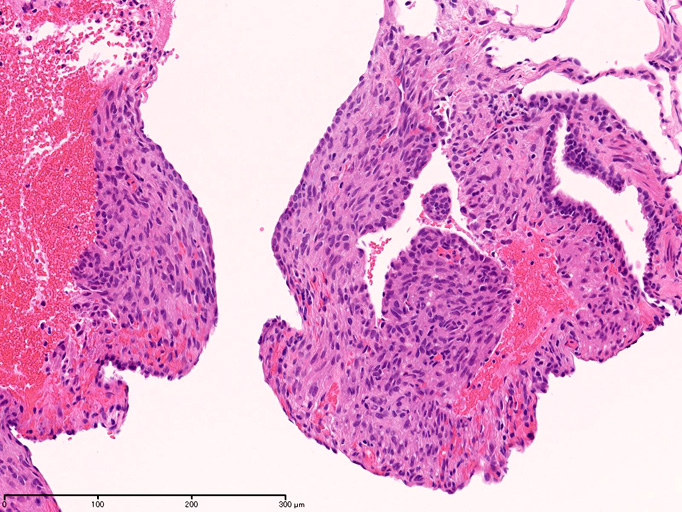

LAMの組織病理

LAMの肺病変

嚢胞周囲または肺血管, リンパ管, 細気管支にそうLAM cellの浸潤, 集簇を特徴とする。LAM cellには2種類が認められ, 小型紡錘形細胞と細胞質の豊富な類上皮様細胞があり, 紡錘型は主に集簇巣の中心に存在し増殖能が高い。 類上皮様LAM cellは辺縁部に多く, 増殖能は低いがHMB45を強く発現している。

LAM cellの免疫染色--SMA, desmin, vimentin(vimentinはいつも陽性とはならない)が陽性となりmuscle lineageであるが典型的な筋細胞と異なり,

嚢胞形成はLAM cellの増殖と関連しており, 細胞が産生するmatrix metalloproteinases(MMPs)による組織破壊によるらしい。